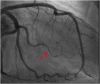

"Cases of SCMR" is a case series on the SCMR website (https://www.scmr.org) for the purpose of education. The cases reflect the clinical presentation, and the use of cardiovascular magnetic resonance (CMR) in the diagnosis and management of cardiovascular disease. The 2022 digital collection of cases are presented in this manuscript.

Keywords: Arrhythmogenic cardiomyopathy; COVID-19; Cardio-oncology; Congenital Heart disease; Coronary artery aneurysm; Hydatid disease; Hypertrophic cardiomyopathy; Metastatic disease; Myocardial. infarction; Myocarditis; Takotsubo; Vaccine associated myocarditis; Viability.